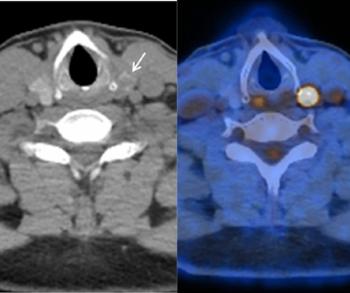

No clear winner has emerged in a head-to-head comparison of whole-body FDG-PET/CT and whole-body 3T MRI for non-small cell lung cancer staging. Unenhanced PET/CT proved better for detecting metastatic lymph nodes and soft-tissue involvement, while MR was more sensitive to the presence of brain and liver metastases.

Both PET/CT and whole-body MR showed 86% accuracy on a per-patient basis for detecting metastases. PET/CT was 48% sensitive and 96% specific for their presence. Three-T MRI was 52% sensitive and 94% specific.

Yi and colleagues found that PET/CT may have been more useful for metastasis detection in lymph nodes and soft tissue because of prominent FDG uptake in lesions in these areas.

Yi credited the higher field strength of 3T MRI and the use of a phased-array cardiac coil for thoracic imaging for improvements compared with earlier studies performed with 1.5T MRI. The better contrast of the MR images compared with PET/CT may have provided improved metastasis detection in the brain, liver, and kidneys, he said.